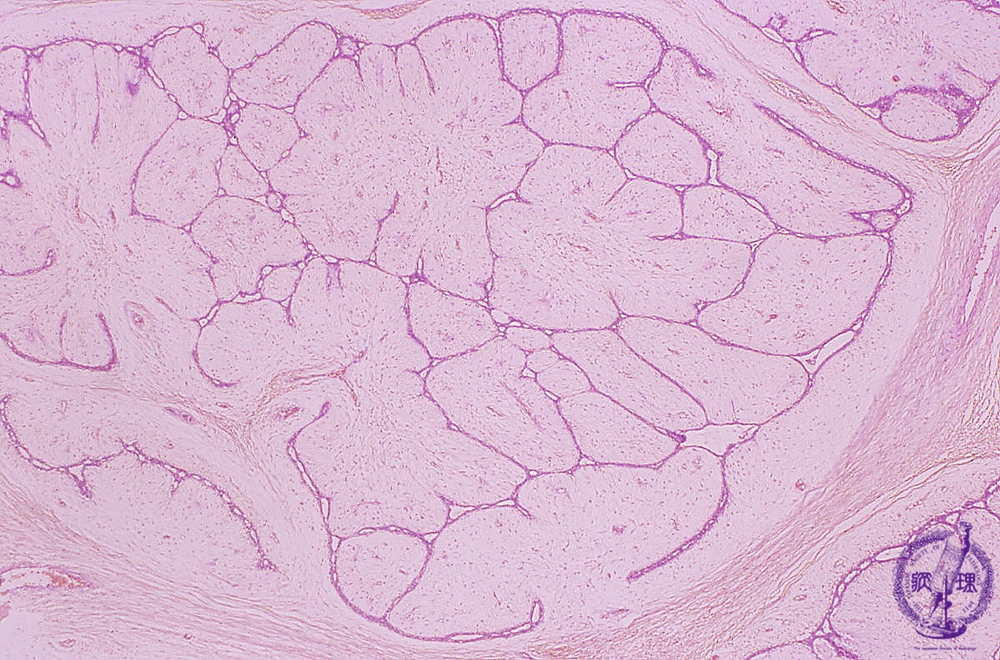

• š(2)Fibroadenoma(intracanalicular type)

Microscopic image(HE stain, low power view):Associated with marked proliferation of stroma. Tumor epithelium proliferates within slit-like or branching spaces among fibrous/edematous stroma.